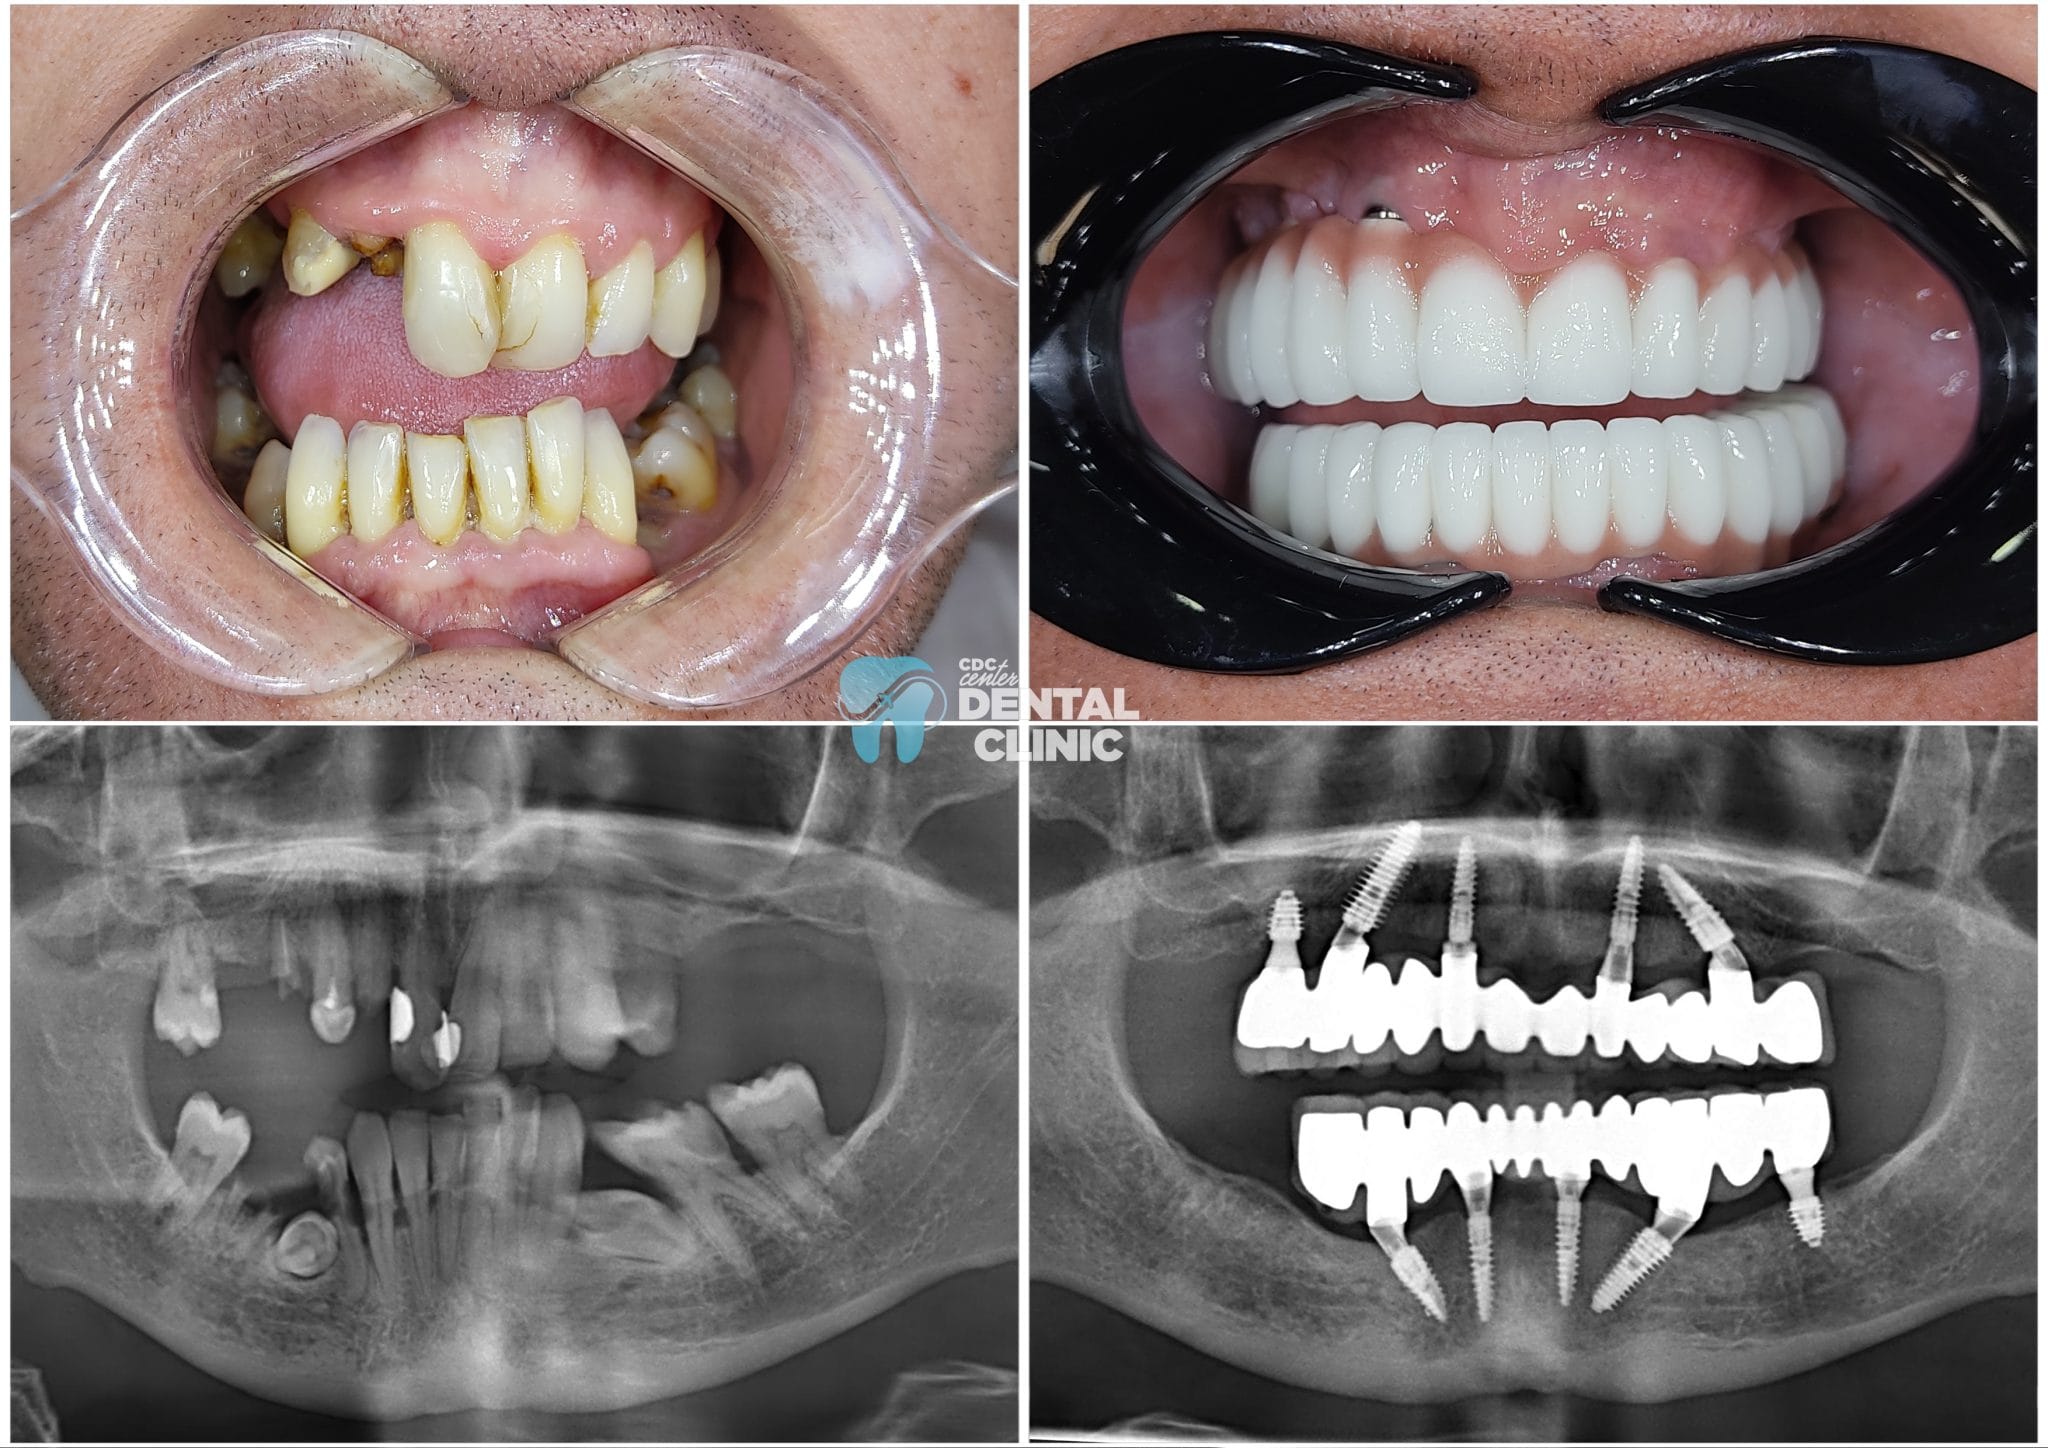

All On 4-6 Implants in Antalya

You do not need to worry about Turkey’s All On 4-6 Implant treatment cost. You will find options suitable for your budget and have your Implant treatment done by the best dentist in Antalya.